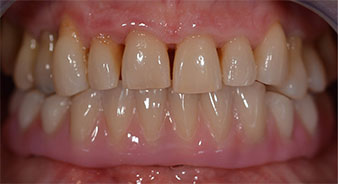

Una vez transcurrido el tiempo necesario para la integración ósea, puede llevarse a cabo la impresión definitiva del implante para realizar la prótesis definitiva de manera acorde (figs. 19 y 20). En este paso, el responsable del tratamiento y el paciente pueden decidir conjuntamente si es preferible un revestimiento cerámico o plástico y una estructura de zircón o de metal. En este caso, dado que el pronóstico de la dentición del maxilar superior era poco claro y la pieza dental 24 estaba elongada, el equipo del Dr. Pascu se decidió por un revestimiento de plástico, ya que, por lo general, es mucho más fácil de ajustar y puede adaptarse a la nueva situación del maxilar superior.